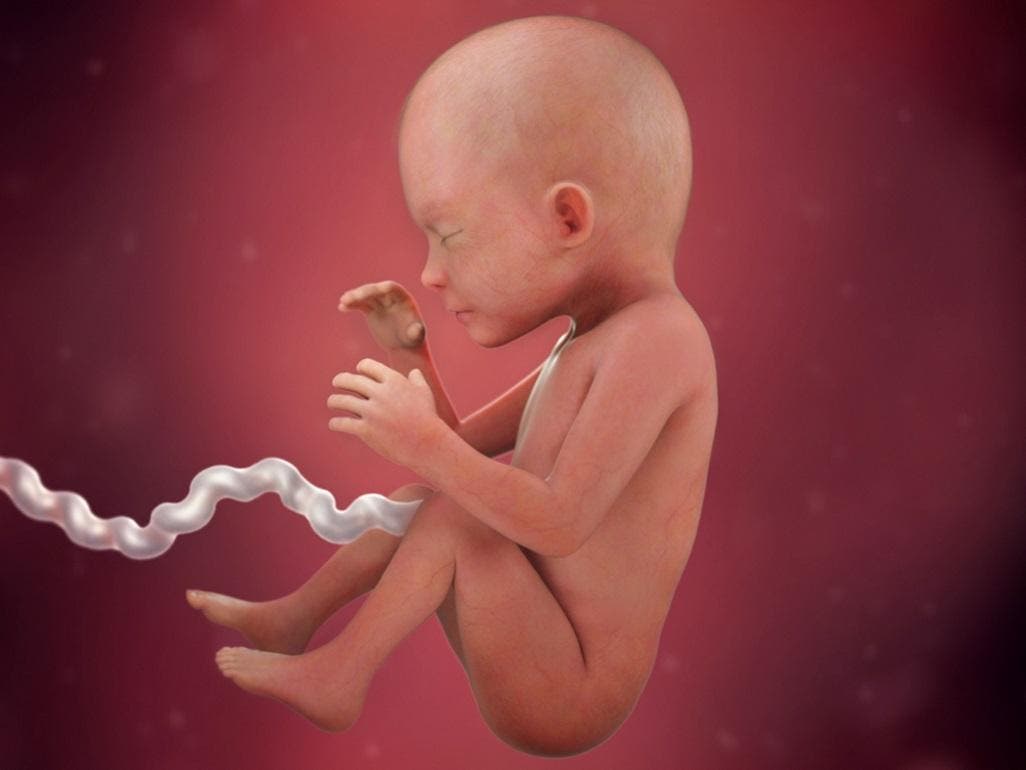

Kaş ve kirpikleri tamamen oluşmuştur. 22 aylık bebek gelişim tablosu. Şimdilerde neredeyse bir hindistan cevizi kadar olan 22 haftalık bebeğin kilosu ve boyunun aşağıdaki aralıkta olması beklenir. Hafta bebeğinizin kilosu 350 gram civarındadır. Bebeğin kilosu ise 450 gram civarındadır. Hafta 27.8 cm 430 gram. Bakalım 21 haftalık bebek neler yapabiliyor… bebeğim ne kadar büyüdü? 22 haftalık bebeğin hareketleri hissedilir mi diye soran anne adaylarına evet yanıtını verebiliriz. Hafta 30 cm 600 gram.

25 haftalık gebelik kaç aylıktır? Bebeğin artık ele avuca gelecek kadar ağırlaştı! Yirmi ikinci haftada bebeğin göz kapakları ve burun delikleri oldukça şekillenmiştir. 22 haftalık gebelikte bebek gelişimi 22 haftalık bebek kilosu ve boyu. 22 haftalık gebelikte bebeğin boyu ve kilosu ne kadar olmalıdır? Kadın doğum doktoru cem fıçıcıoğlu anlatıyor.

Haftanın sonunda artık bebeğin boyu yaklaşık 30 cm. 27 aralık 2021 hamilelikte bebek sağlığı kategorisinde mercimeginannesi13 (46 puan) sordu. Hafta 30 cm 600 gram. Gülümserken veya bebeğin yüzünü asmışken görüntülerini yakalamak 22. Hafta 27.8 cm 430 gram. Gebelikte 22.hafta bebek gelişimi göz kapakları ve burun deliklerinin şekillenmeye devam etmeketedir.kaş ve kirpikleri artık tamamen oluşmuştur.

Hafta hamilelik döneminde bebeğin boyu ve kilosu ne kadardır? Kalp atışları da daha düzenli bir hale gelmiştir. 22 aylık bebeğin gelişimi fiziksel, bilişsel sosyal ve duygusal alanı kapsar. Gebelikte hafta hafta bebeğin kilosu ve boyunu hesaplama. Gülümserken veya bebeğin yüzünü asmışken görüntülerini yakalamak 22. Yirmi ikinci haftada bebeğin göz kapakları ve burun delikleri oldukça şekillenmiştir.

Tat alma ve dokunma duyuları gelişmeye devam ediyor. Hafta 27.8 cm 430 gram. 22 haftalık bebek ne kadar olur? Bebeğinizin boyu 29 cm, ağırlığı ise 400 gram oldu.tüm organları artık daha da gelişti ve fonksiyonel bir hal almaya başladı. 25 haftalık bebeğin boyu 34 cm’ e ulaşırken ağırlığı da 700 gramı bulur. Bu konu şimdiye dek 822 kez görüntülenmiş, 10 yorum ve 0.

Bebeğinizin boyu 29 cm, ağırlığı ise 400 gram oldu.tüm organları artık daha da gelişti ve fonksiyonel bir hal almaya başladı. Bebeğiyle iletişim kurmak isteyen anneler, ona müzik dinletebilir ya da hikaye okuyabilir. Bebeğin beyin dokusu ve iç organları 22. Ve kilosu da yaklaşık 480 gram dolaylarında! 30 ocak 2020 hamilelik dönemi genel kategorisinde özge uygar (352 puan) sordu. 25 haftalık gebelikte bebeğin boyu ve kilosu ne kadar olmalıdır?

Gebelik takibi sırasında anne adaylarının en fazla merak etikleri konulardan birisi de bebeklerinin sağlıklı gelişimlerinin yanında hamilelik haftasına göre bebeğin boyunun ve ağırlığının ne olduğudur. 22 haftalık gebelikte bebeğin boyu yaklaşık 30 cm, ağırlığı ise 500 gramdır. Bebeğin beyin dokusu ve iç organları 22.

Bebeğin vücudu her gün biraz daha yenidoğan görünümü kazanır. Bakalım 21 haftalık bebek neler yapabiliyor… bebeğim ne kadar büyüdü? Haftada artık bebeğin kaşları ve saçları daha belirgindir.

22 haftalık gebelikte bebeğin boyu yaklaşık 30 cm, ağırlığı ise 500 gramdır. 22 haftalık bebek ultrason görüntülerinde uyurken veya hareket halinde görüntülenebilecektir. Anne karnında bebeğin boyu ve kilosu.

Gebelik takibi sırasında anne adaylarının en fazla merak etikleri konulardan birisi de bebeklerinin sağlıklı gelişimlerinin yanında hamilelik haftasına göre bebeğin boyunun ve ağırlığının ne olduğudur. Hafta 30 cm 600 gram. Kaş ve kirpikleri tamamen oluşmuştur.

Hafta 26.7 cm 360 gram. Gebelikte 22.hafta bebek gelişimi göz kapakları ve burun deliklerinin şekillenmeye devam etmeketedir.kaş ve kirpikleri artık tamamen oluşmuştur. Anne karnında bebeğin boyu ve kilosu.

Tat alma ve dokunma duyuları gelişmeye devam ediyor. Bebeğiyle iletişim kurmak isteyen anneler, ona müzik dinletebilir ya da hikaye okuyabilir. 440 gram kaş tüyleri ortaya çıkar ama tüyler oldukça incedir.

Bu dönemde bebek artık annesini çok rahat bir şekilde duyabilir. Yirmi ikinci haftada bebeğin göz kapakları ve burun delikleri oldukça şekillenmiştir. Bebek her bir alanda sağlıklı bir gelişim seyretmelidir.

Gebelikte 22.hafta bebek gelişimi göz kapakları ve burun deliklerinin şekillenmeye devam etmeketedir.kaş ve kirpikleri artık tamamen oluşmuştur. Hafta 26.7 cm 360 gram. Bebeğiniz artık tıpkı yeni doğan bir bebeğe benzemeye başladı bile.

Bebeğiniz başparmağını emebilir, beslenme kordonunu tutabilir, kavrama yeteneği gelişebilir, hıçkırabilir. 22 haftalık bebek kaç gram olur? 22 aylık bebek gelişim tablosu.